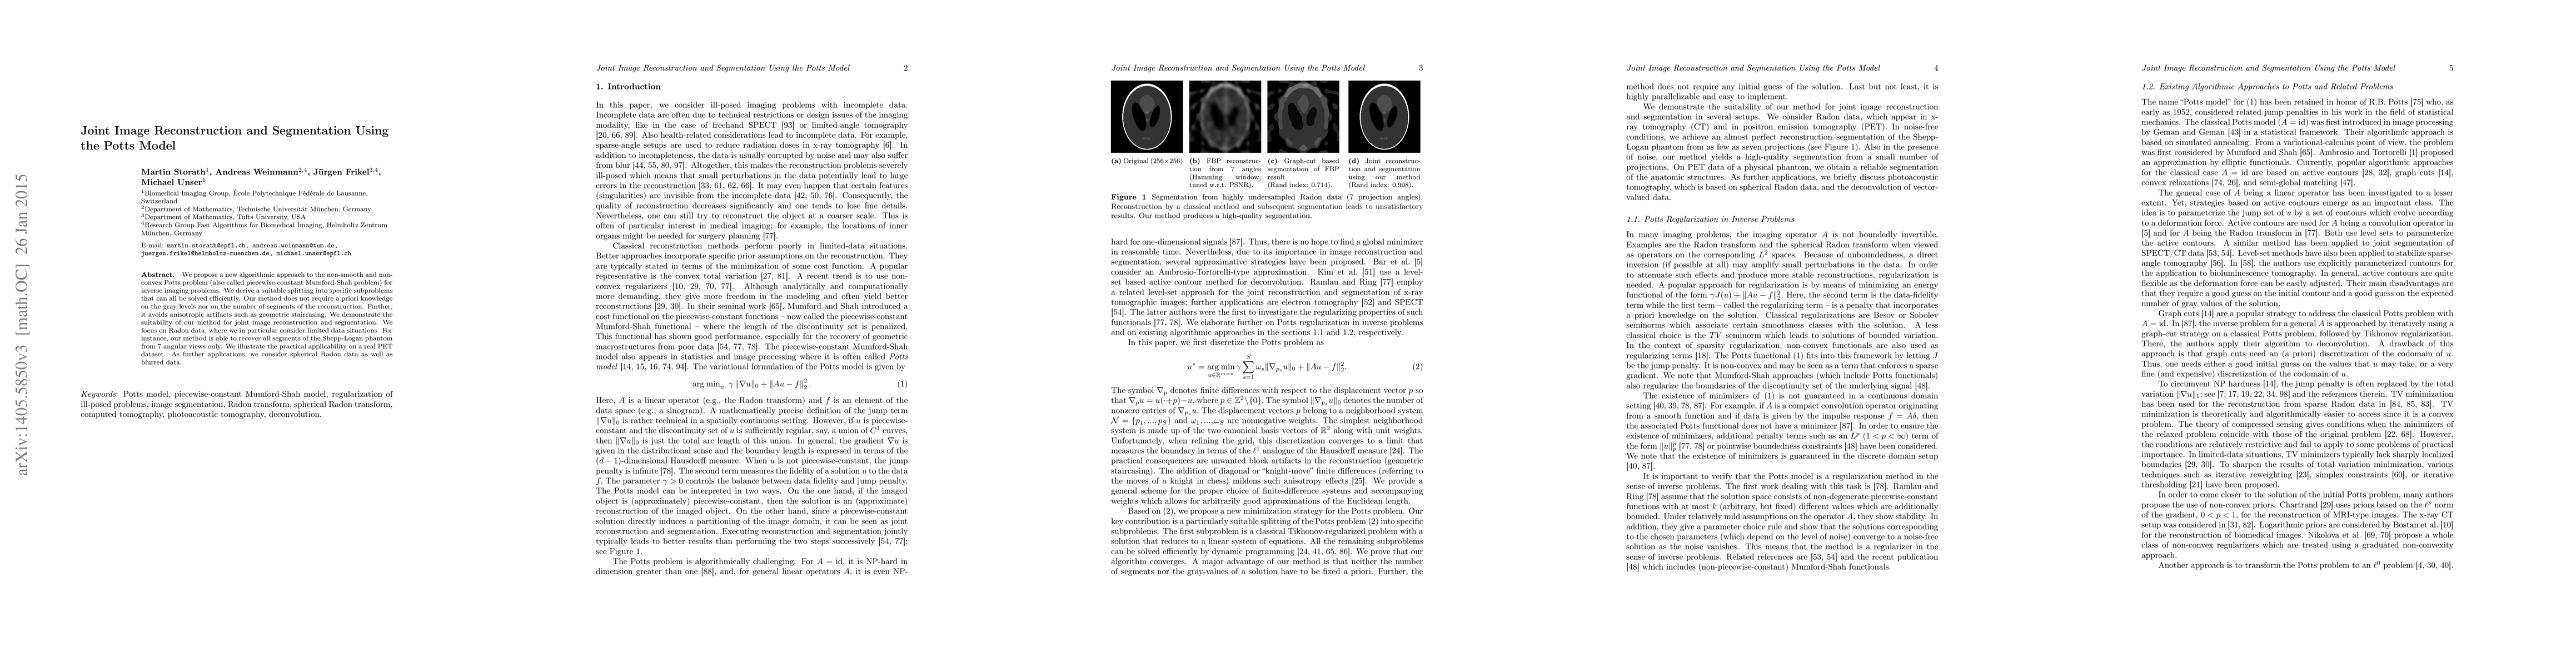

We propose a new algorithmic approach to the non-smooth and non-convex Potts problem (also called piecewise-constant Mumford-Shah problem) for inverse imaging problems. We derive a suitable splitting into specific subproblems that can all be solved efficiently. Our method does not require a priori knowledge on the gray levels nor on the number of segments of the reconstruction. Further, it avoids anisotropic artifacts such as geometric staircasing. We demonstrate the suitability of our method for joint image reconstruction and segmentation. We focus on Radon data, where we in particular consider limited data situations. For instance, our method is able to recover all segments of the Shepp-Logan phantom from $7$ angular views only. We illustrate the practical applicability on a real PET dataset. As further applications, we consider spherical Radon data as well as blurred data.